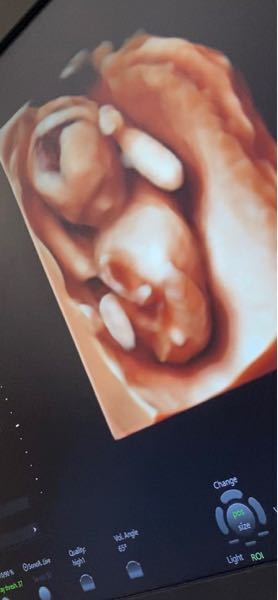

4dエコー 22週 に行ってきました Violet And Honey Fizz

初めての4dエコー 性別判明 ニート主婦の妊娠生活 楽天ブログ

性別判明 4dエコー Eriko S Blog プロトラベラーerikoのブログ Lifestyle

4dエコー検証 やっぱり男の子 Camelliaのゆるゆる育児記録 18 4長女出産 4長男出産

妊婦健診 4dエコー写真と妊娠7ヶ月経過 元にゃーごの育児生活

17w6d 初の4dエコー 画像有 3歳差男の子 男の子育児日記

4dエコーで初めて見たわが子の顔 先生が撮った最高の1枚 たまひよ